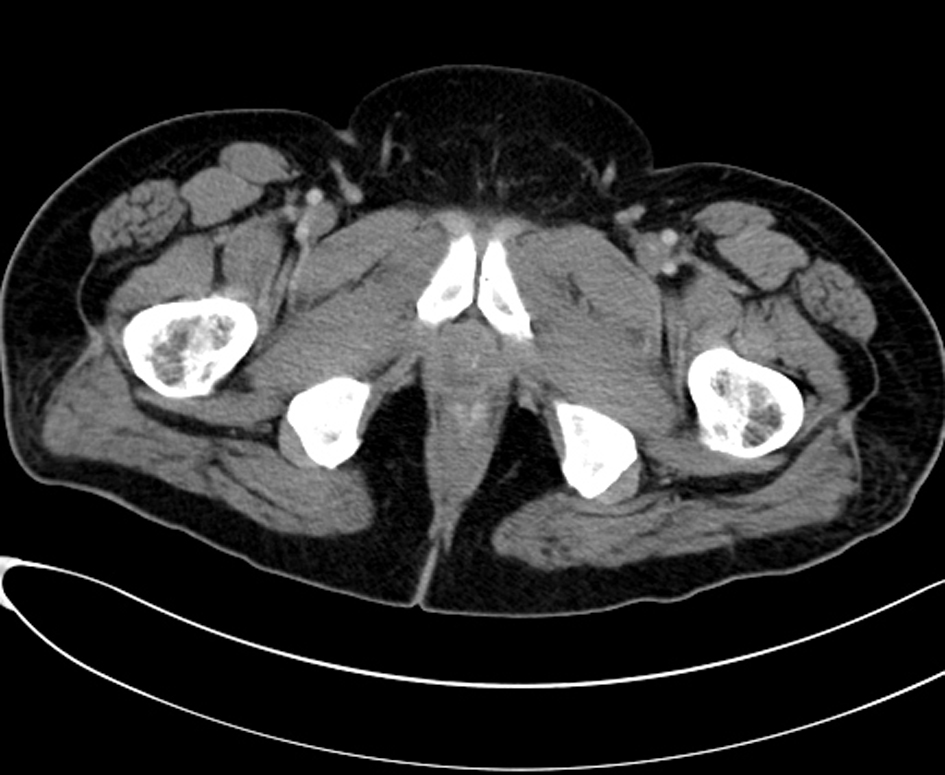

Computed tomography (CT) scan examination of the abdomen and pelvis was performed after administration of intravenous (IV) contrast material in portal venous phase which shows an empty scrotal sac with absence of the testicles and spermatic cord bilaterally (Fig. 1). A large homogenous mass is identified within the retro peritoneum of the right lower abdominal quadrant associated with small central area of low attenuation could represent an areas of cystic necrosis. No associated calcification is seen (Fig. 2). Small oval and homogenous structure is seen within the left aspect of the hemi pelvis just adjacent to the inguinal ring which represents a small atrophied left testicle with no masses (Fig. 3). There are multiple homogenous and matted lymph nodes metastasis located within the right Para-aortic region in close relation to the right renal hilum (Fig. 4).

![]() Click for large image | Figure 1. Computed tomography (CT) scan examination shows an empty scrotal sac with absence of the testicles and spermatic cord bilaterally. |